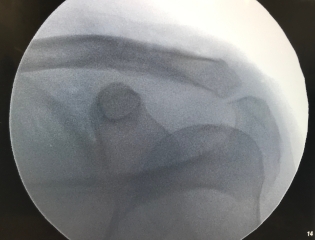

Grade 5 AC separation equivalent with distal clavicle fracture

Tensioned cerclage repair of AC joint with bone tunnels

AC joint repair can performed arthroscopically by drilling a hole in the distal clavicle and coracoid. A metal button is placed on top of the clavicle and below the coracoid process of the scapula. A strong suture is tied between the two which reduces the AC joint.